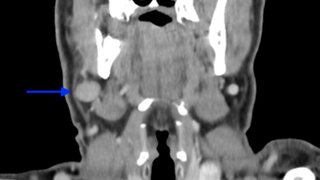

Studie zur Kopf-Hals-Tumoren-TherapieIst die Chemo wirklich immer nötig? Bei der Behandlung von Tumoren im Kopf-Hals-Bereich ist heute die Immuntherapie mit Checkpoint-Inhibitoren zusätzlich zu Bestrahlung und Chemotherapie üblich – doch ist letztere immer nötig? 28.06.2021 Zahnmedizin

Patientenfall in der MKG-ChirurgieMetastase in der Mundschleimhaut Die klinische Untersuchung ließ auf ein Plattenepithelkarzinom schließen, differenzialdiagnostisch kam auch eine Epulis in Betracht. Anamnestisch zeigte sich eine schwere langjährige Vorerkrankung. 09.06.2021 ZahnmedizinPraxis